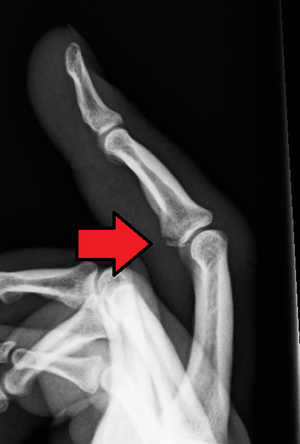

Greenstick Fracture - एका बाजूने फ्रॅक्चर, पण हाड वाकल्याने ते पूर्ण न तुटणे. हे फ्रॅक्चर लहान मुलांमध्ये जास्त आढळून येते कारण त्यांची हाडे लवचिक असतात.

Torus Fracture - यात हाड तुटत नाही पण हाडाचा आकार बदलल्याने वेदना होतात.